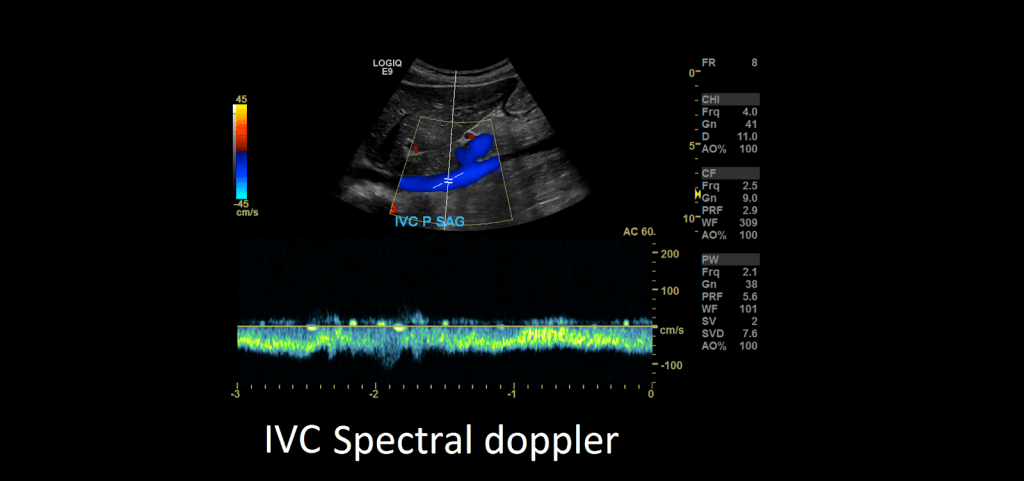

After you’re done evaluating the aorta, turn your attention to the inferior vena cava. Capture images in sagittal and transverse in grayscale, color and spectral Doppler.